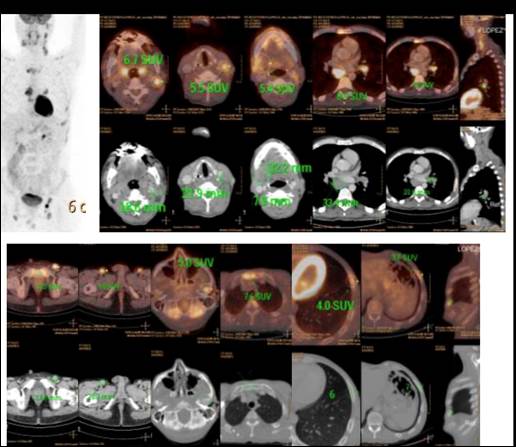

Se completó estadificación con PET-TC. El estudio mostró imágenes de concentración patológica del radiotrazador en múltiples adenopatías hipermetabólicas y en focos hipermetabólicos óseos, que interpretamos como vinculados a compromiso nodal y extra nodal de enfermedad linfoproliferativa (Figura 1).

Figura 1. Hallazgos del PET-TC al diagnóstico